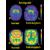

L'esperimento, presentato da Schwartz al Convegno di Neuroscienze in corso a San Diego, offre speranze per persone che hanno subito amputazioni o lesioni spinali che le hanno lasciate paralizzate. A parole il processo e' semplice: un sensore applicato al cervello della scimmia capta segnali elettrici da un gruppo di cellule della corteccia motoria, la porzione del cervello che controlla il movimento volontario. Un programma di computer interpreta i segnali e manda i comandi appropriati al braccio meccanico.